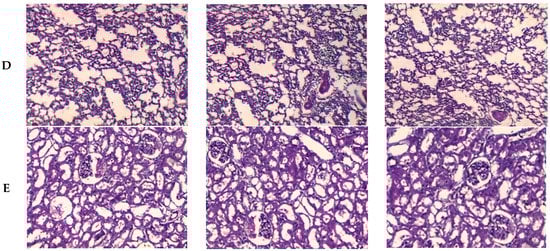

3.3.5. Anatomopathological Exam